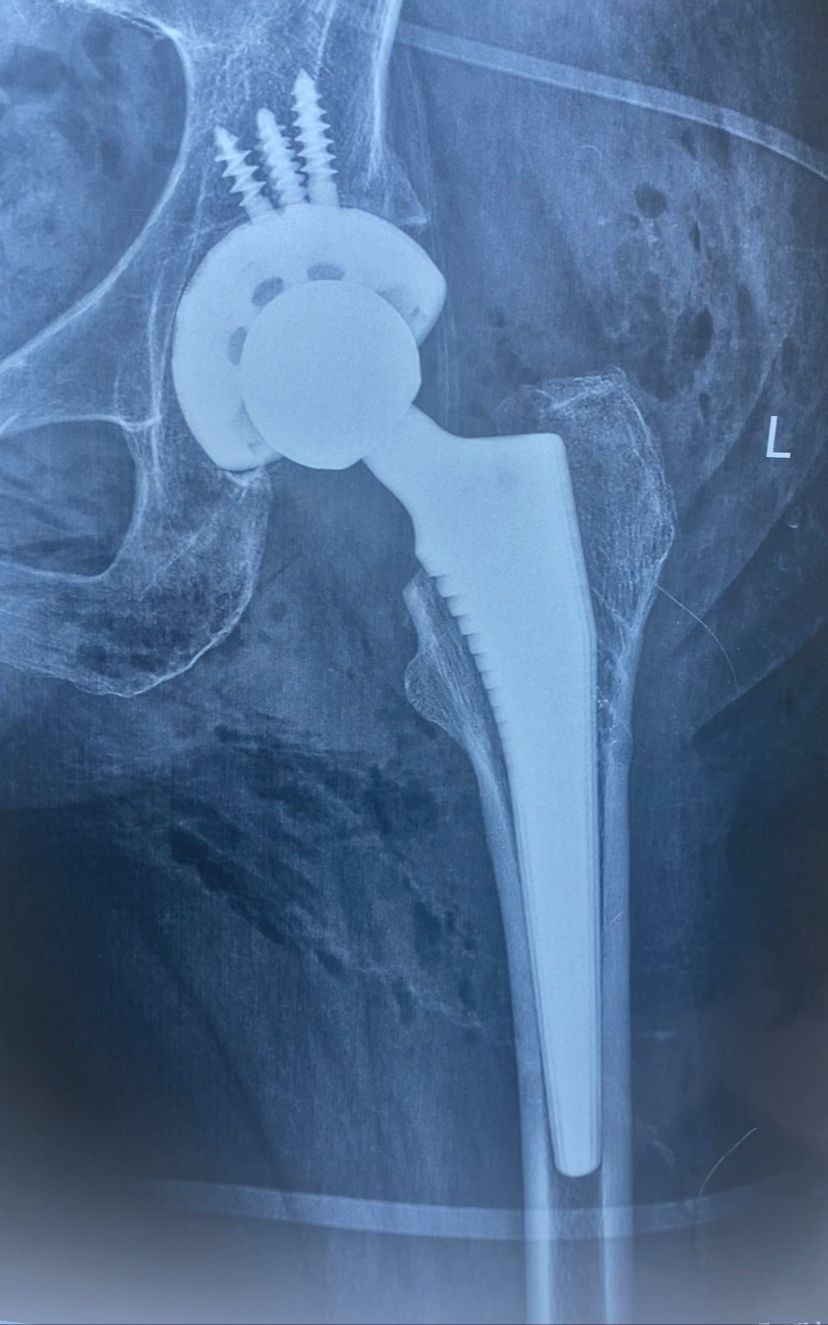

تم إجراء تثبيت داخلي لكسر بالحوض بمسامير عام ٢٠٠٩

في عام ٢٠٢١ بدأت تشعر بالام متزايدة بالمفصل كما بينت الاشعات تآكل به

عام ٢٠٢٤ كانت الالام مع المشي اصبحت شديدة مما استدعى عمل تغيير كامل للمفصل